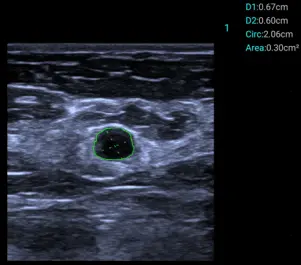

Smart Calc

Полуавтоматично измерване на диаметър и площ на лезии.